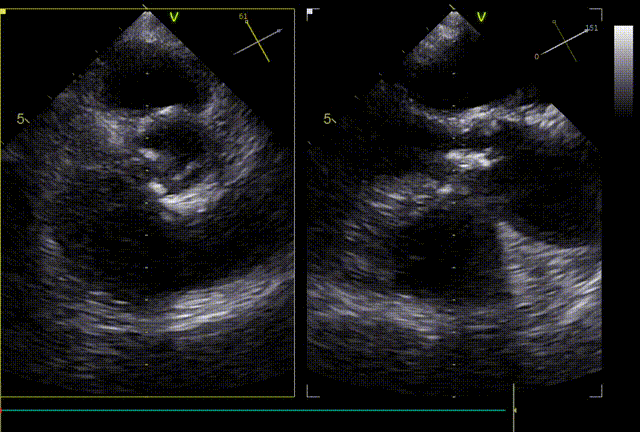

术前超声:

发生瓣叶切割,无窦侧瓣叶切割,Type0结构形变为类三叶瓣结构。